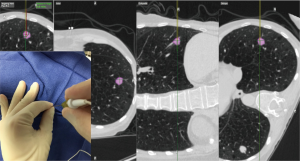

Percutaneous biopsy

The EM navigational needle is also tip-tracked in real time to the target lesion. Pre-procedural planning is performed as described above. The needle trajectory is guided by multiplanar CT scan images and the virtual 3D reconstruction images. Once in the lesion the needle stylet (sensor) is removed. Fine needle aspiration is performed for rapid on-site evaluation (ROSE) followed by larger biopsies. Multiple core samples are obtained using a 20 G automatic biopsy needle (Figure 6). Specimens are typically placed in formaldehyde for pathological analysis. Post procedure evaluation with chest ultrasonography or conventional chest radiography is advised in order to exclude complications such as pneumothorax.

Dye marking prior to surgery

Several techniques exist to localize pulmonary nodules for operative excision and they typically require a percutaneous approach to place pleural markers, coils, hook wires or radioactive markers but these procedures, unfortunately, have a high rate of pneumothorax. The premise for use of ENB for localization is that after the lesion is located during navigation and methylene blue is injected near the lesion. The surgeon resects the marked area during the same operative and anesthesia time, and intraoperative frozen sectioning confirms successful resection. This approach greatly aids lung preservation, length of procedural, anesthesia and operating room times, limits cost and makes the work-up and management for a pulmonary nodule efficient for the patient, all while minimizing morbidity (30). Krimsky et al. have recently published an approach whereby they “tented” the sub-pleural space adjacent to the nodule with the locatable guide and extended working channel under fluoroscopy and a 25 gauge sclerotherapy needle was used to inject 0.5 mL of either indigo carmine or methylene blue dye at the site. Following marking, the patients were taken to the operating room for a minimally-invasive resection either by video-assisted thoracoscopic surgery (VATS) or robotic-assisted thoracoscopic surgery (RATS) approaches with or without an anatomic resection and lymph node dissection. They found the dye marker outlined the area of interest 81% of the time in 22 patients. One patient had diffuse dye marking of the parietal pleura and two patients the dye was not visualized. The nodules studied had a mean size of 13.4 mm (range, 7–30 mm). No patient had to be converted to an open procedure (31).

A similar technique was published the same year by Bolton et al. They evaluated 19 patients who underwent ENB localization and dye marking prior to robotic resection. Their approach differed in that they marked the lesion as well as the nearest pleural surface. Mean size of lesions was 18 mm (range, 8–40 mm and only four patients with lesions >20 mm, all of which were ground glass nodules/masses) (32). Finally, earlier this year, Anayama et al. published a technique for the use of thoracoscopy following injection of indocyanine green (ICG) that is delivered bronchoscopically via ENB guidance to a pulmonary nodule without injuring the visceral pleura. They have tested this protocol on three live pigs whereby they created pulmonary nodules with 0.3 mL of 5% agar containing iopamidol. ENB was used to then bronchoscopically inject 0.1 mL of ICG to the area of the nodule. After 6 hours, the lung was examined with a thoracoscope that has near infrared capabilities. The nodules were successfully located and were found to be within 3.3±0.95 mm of the nodule. The benefit of this approach is that ICG is not affected by color changes of the pleura that can occur with anthracosis or underlying pulmonary disease. Contrary to the use of fiducial markers, micro-coils or hook-wires this approach did not result in pneumothorax. ICG can also notably be confirmed with CT scan prior to surgery (33).